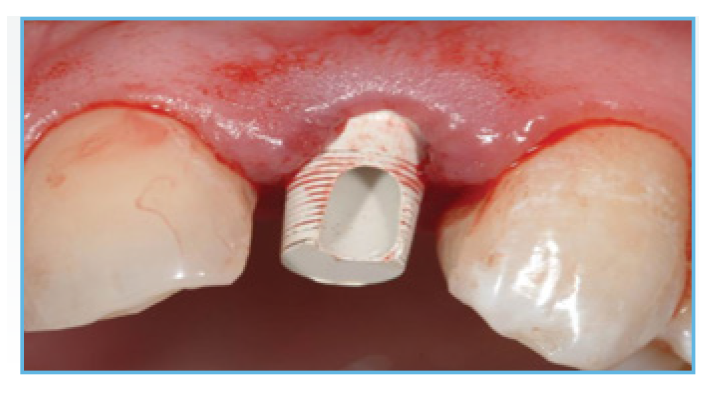

Fig. 1. NanoTite® Certain Implant in place. The bone was profiled around the interface.

Fig. 2. A PreFormance Post was seated into the implant.